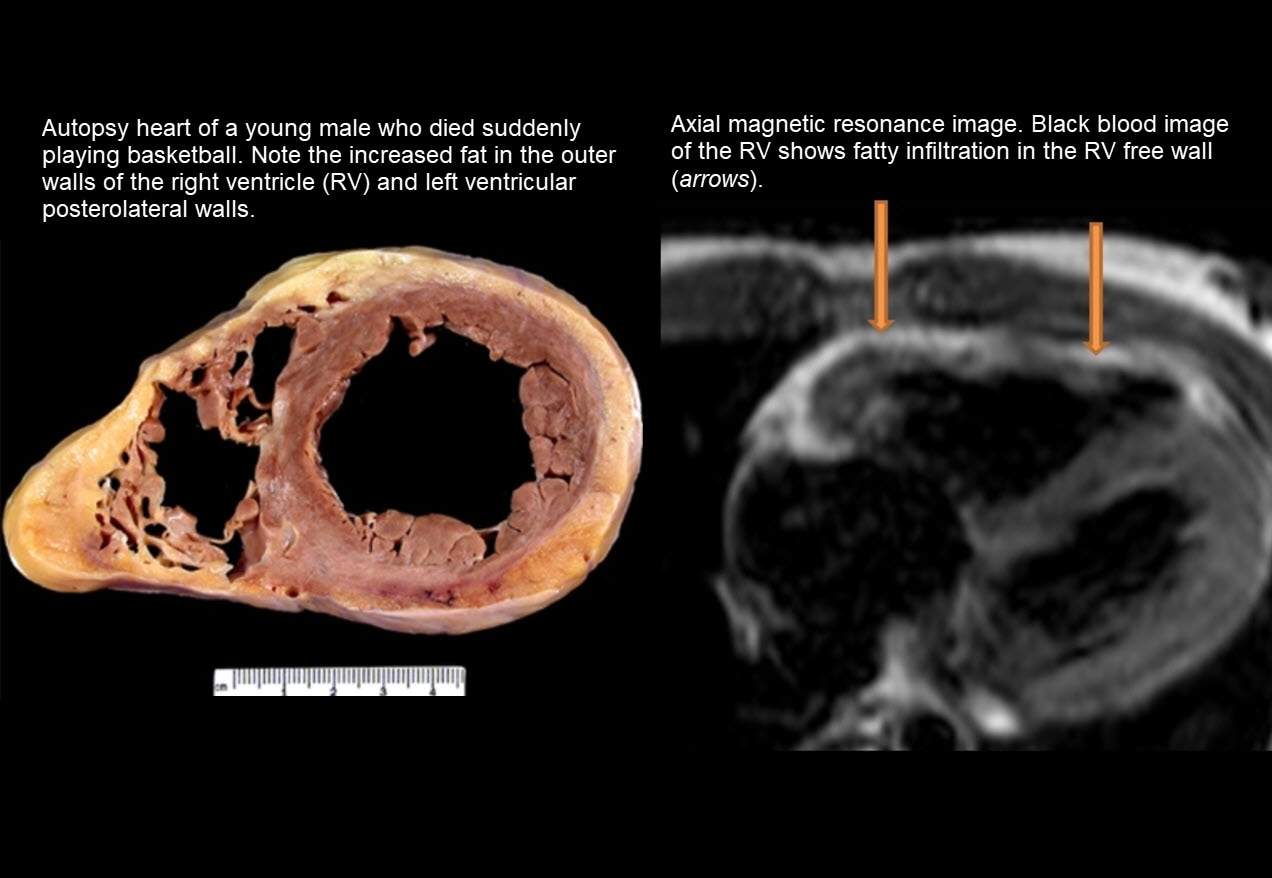

Sudden Cardiac Death In Young Athletes – Howard J. Luks, MD

www.howardluksmd.comSudden cardiac death in young athletes – Howard J. Luks, MD

www.howardluksmd.comSudden cardiac death in young athletes – Howard J. Luks, MD

Sudden Cardiac Death

reference.medscape.comSudden Cardiac Death

reference.medscape.comSudden Cardiac Death